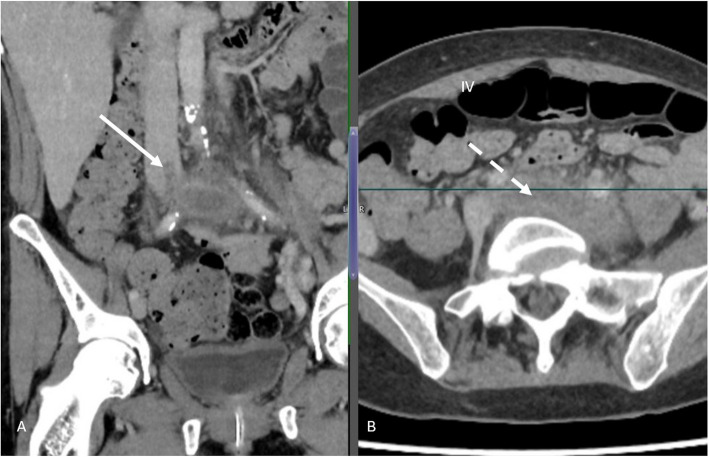

Abstract Image